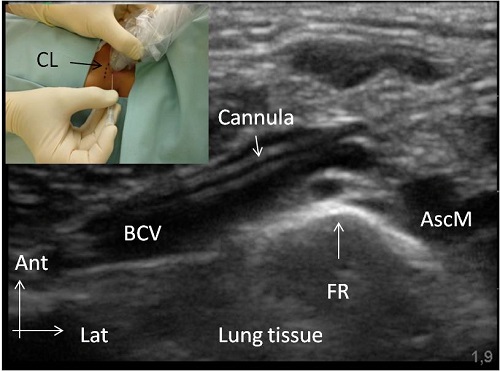

22-gauge i.v. cannula (Abbocath) within the left BCV of a 3 kg infant. Small picture: Right-handed operator maneuvering the i.v.cannula without attached syringe with the right hand while holding the US probe in the left hand. CL, clavicle. Ultrasound image: BCV, brachiocephalic vein; FR, first rib; AscM, anterior scalene muscle.